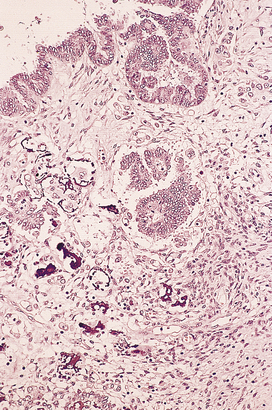

image

Fig. 19.5 Koilocytosis. Cytoplasmic vacuolation and pyknotic nuclei indicative of human papillomavirus infection of the cervix.